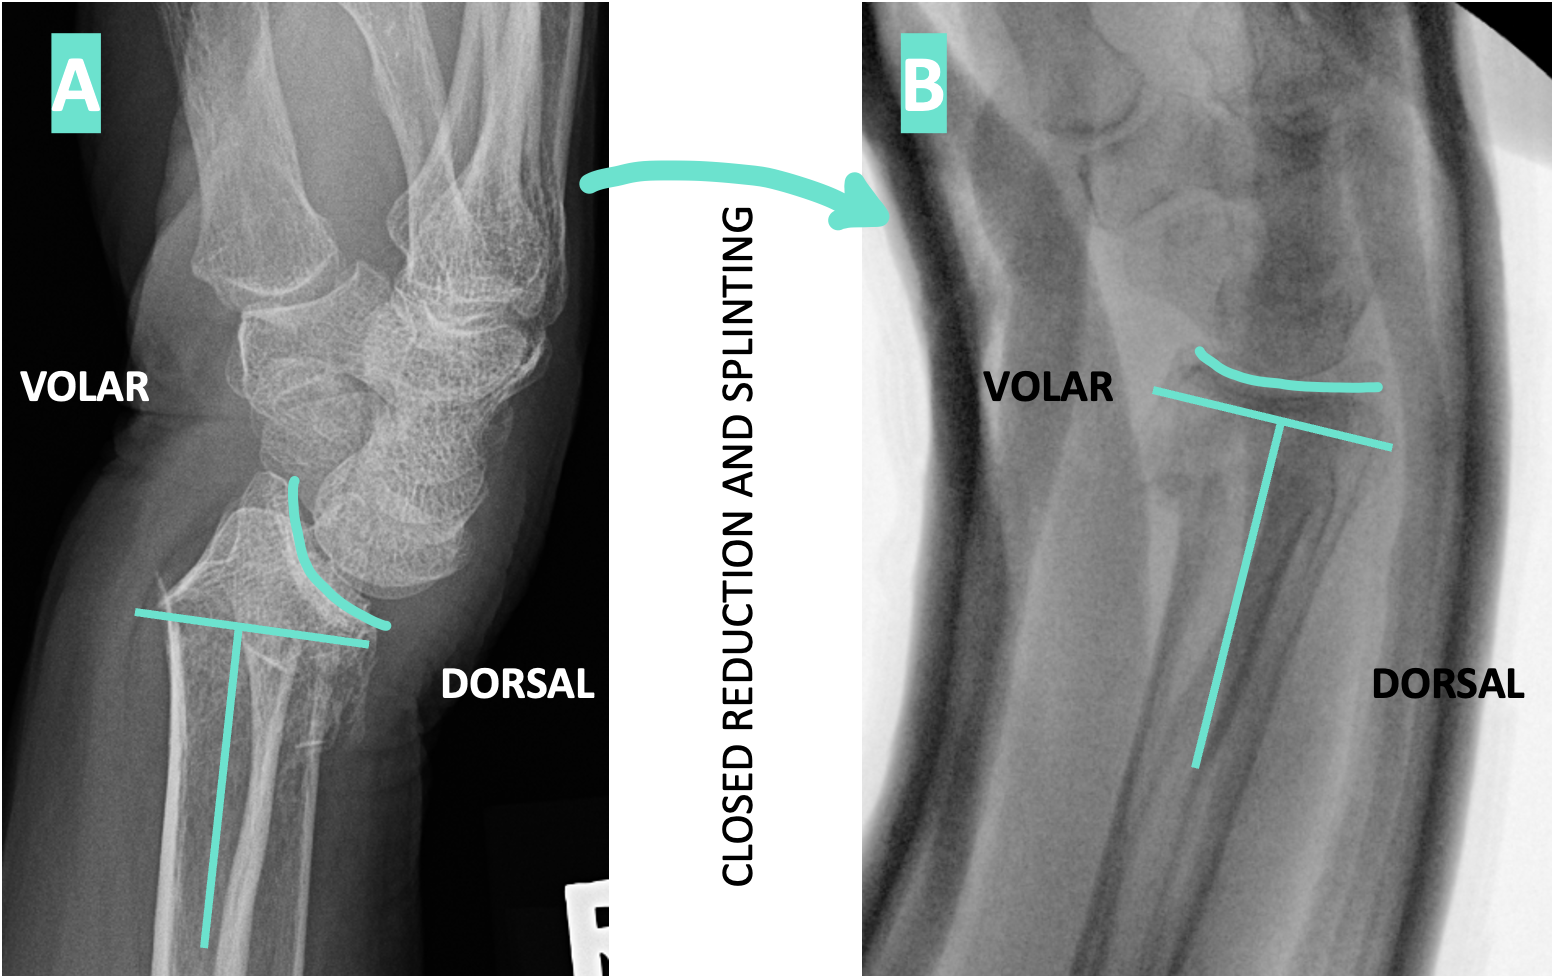

On the lateral view you determine which side is volar and which is dorsal. There is significant dorsal angulation - IT’S TIME FOR CLOSED REDUCTION AND SPLINTING! No need to ask for permission from ortho - you got this!

Check out those post-reduction xrays! What an improvement!! The patient is referred to Ortho for follow up. The splint that you placed could stay on for 3 weeks until the fracture is healed enough to transition to a short arm cast.